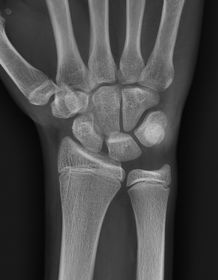

| PA Wrist | wrist externally rotated - joint spaces closed, proximal metacarpals superimposed, carpals superimposed radiocarpal joint is closed |

| Oblique Wrist | over rotation radial styloid is not seen in profile |

| Lateral Wrist | under rotation - radius and ulna are not superimposed, hand is internally rotated |

| PA Wrist | ANATOMY: all carpals including midmetacarpals and distal radius/ulna CRITERIA: true PA is marked by symmetry of proximal metacarpals carpals should be free of superimposition of the metacarpals and radius/ulna POSITIONING: CR perpendicular @ midcarpals |

| Oblique Wrist | ANATOMY: carpals on lateral side of wrist, scaphoid CRITERIA: scaphoid well demonstrated 45 degree obliquity POSITIONING: CR perpendicular @ midcarpals |

| L | CRITERIA: radius/ulna should be superimposed thumb should be forward metacarpals superimposed POSITIONING: CR perpendicular @ midcarpals |